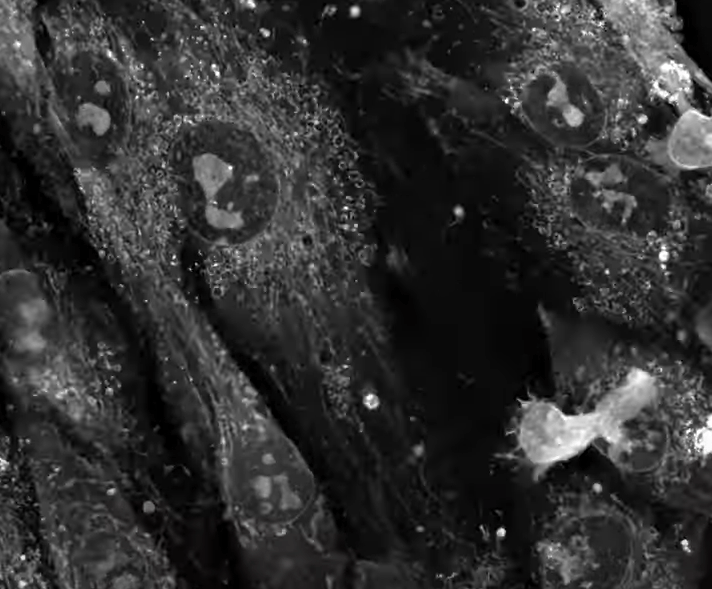

NanoLive 的全息斷層掃描技術是一種結合全息術和斷層掃描原理的新型成像技術。它利用物體對光的折射率差異 (Refractive Index Difference),從多個角度獲取全息影像 (Holographic Images),然後利用計算機重建出物體的三維 (3D) 折射率分佈圖 (RI Tomogram)。

NanoLive 的 3D Cell Explorer 使用低功率雷射 (Low-power Laser, 520 nm, 0.1 mW),從多個角度照射樣本,測量穿過細胞的光波的相位延遲 (Phase Delay)。由於細胞內不同結構,例如細胞核、細胞質、細胞膜等,具有不同的折射率 (RI),因此光波在穿過這些結構時會產生不同的相位延遲。

• 內源性對比 (Intrinsic Contrast):細胞內的各種結構 (例如細胞核、細胞質 、細胞膜 、細胞器 等) 具有不同的折射率 (RI),這使得全息斷層掃描無需染色即可區分這些結構。通過測量細胞內各區域的折射率分佈 (RI Distribution),可以了解細胞的組成和結構。

• 動態追蹤 (Dynamic Tracking):由於全息斷層掃描可以快速地獲取細胞的三維 (3D) 折射率分佈 (RI Distribution),因此可以實時追蹤細胞內部的動態變化 (Dynamic Changes),例如細胞器的運動 (Organelle Movement)、物質的運輸 (Material Transport)、細胞的形變 (Cell Deformation) 等。

• 細胞結構與功能研究 (Cell Structure and Function Study):觀察細胞內部的精細結構 (Subcellular Structures),例如細胞核 (Nucleus)、細胞器 (Organelles)、細胞骨架 (Cytoskeleton) 等,研究它們的結構與功能之間的關係 (Relationship)。